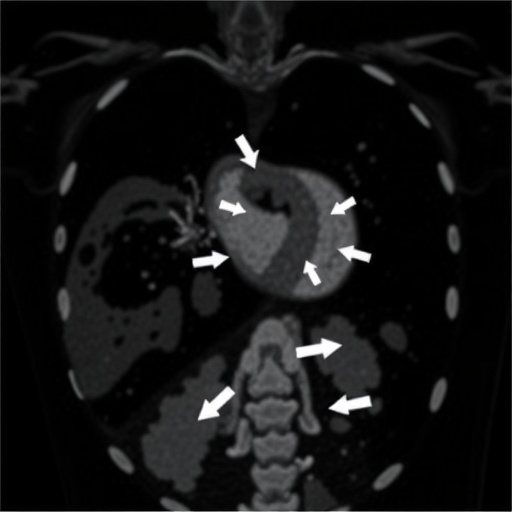

The researchers also delved into the dynamic interplay between ventricular interdependence and septal morphology, observed through echocardiographic imaging. Altered septal curvature and interventricular septal shifts were recurrent in severe cases, reflecting the pathophysiological strain imposed by high pulmonary pressures. These insights into ventricular geometry alterations illuminate substrates for future targeted therapies aimed at ameliorating cardiac loading conditions in CDH neonates.